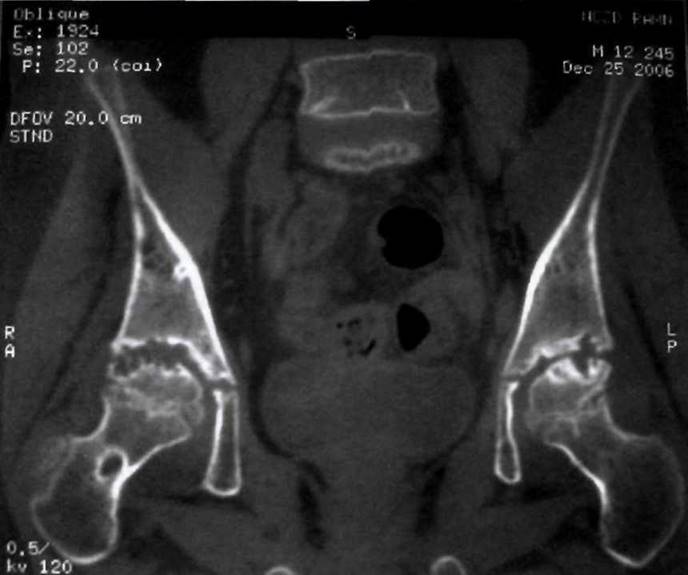

Рис. 23-22. Двусторонний сакроилеит у больного ЮАС: эрозии, расширение щелей крестцово- подвздошных сочленений, субхондральный склероз. Патологические изменения определяются в обеих сочленяющихся костях, но более выражены в подвздошных костях.